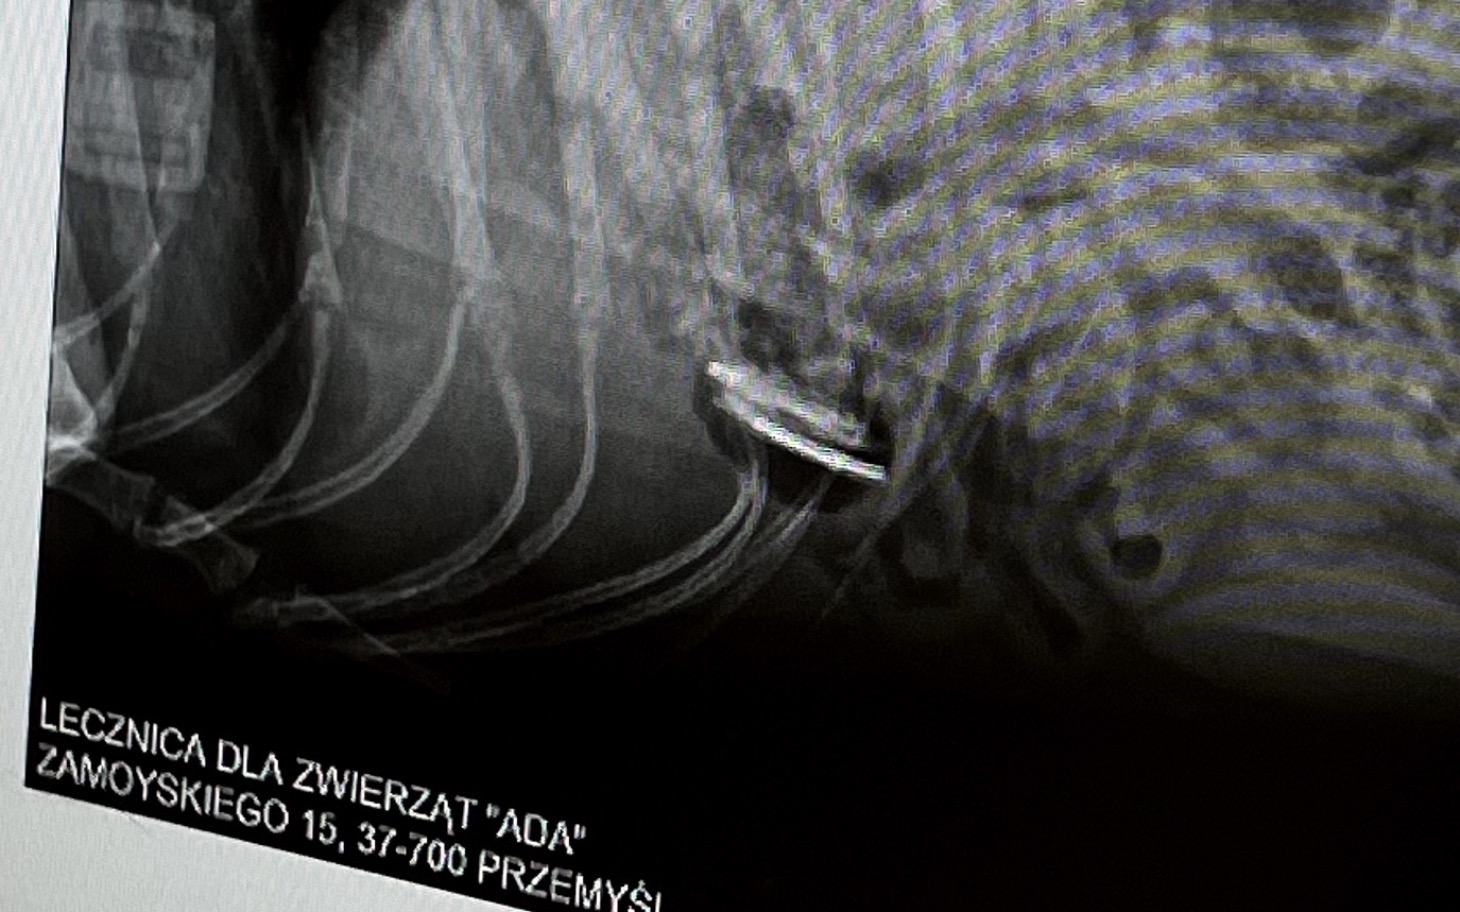

Emergency. Jędruś nagle źle się poczuł. Opiekunowie zareagowali natychmiast i dzięki temu szybko trafił do lekarza. Badanie ujawniło dramatyczną prawdę. W jego brzuchu utknęło ciało obce. Każda godzina zmniejsza jego szanse.

Potrzebujemy pieniędzy na pilny zabieg i dalszą opiekę. To koszt, którego nie jesteśmy w stanie pokryć bez wsparcia.